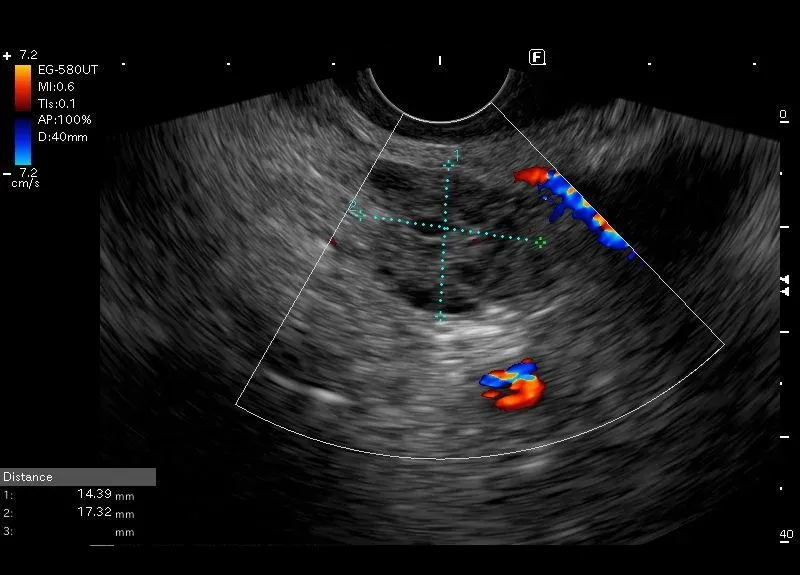

Widoczna w ciaśni trzustki dobrze odgraniczona zmiana torbielowata złożona z  licznych drobnych przestrzeni bezechowych, przedzielonych komponenta litą, bez przepływu w opcji power doppler. Opisana zmian ma wielkości około 18/16 mm. Została odnaleziona u bezobjawowej pacjentki wieku 88 lat, u której nie opisano innych zmian patologicznych w trzustce.

Zmiana torbielowata trzustki o morfologii SCN microcysticum (serous cysticneoplasm).